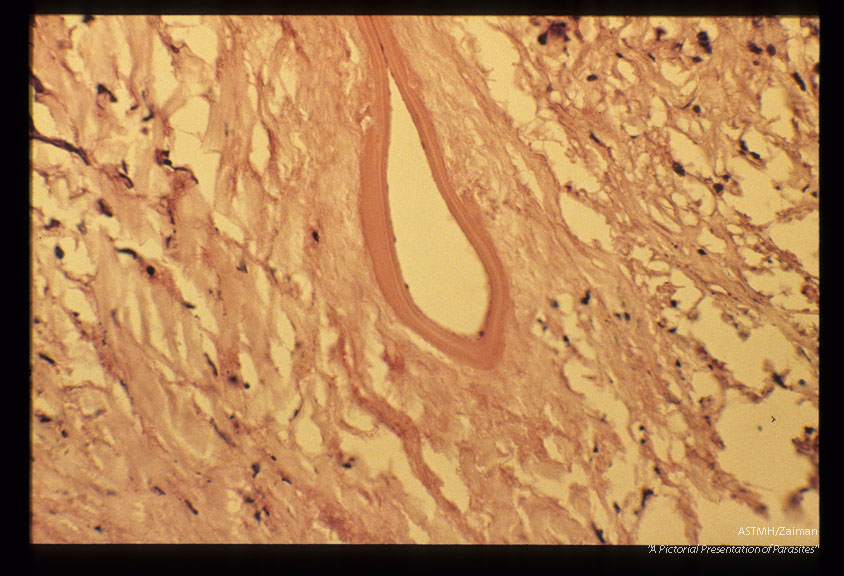

Gross and microscopic photos of human liver from Minnesota where about one half of the red foxes are infected.

Echinococcus multilocularis

Description: Gross and microscopic photos of human liver from Minnesota where about one half of the red foxes are infected.